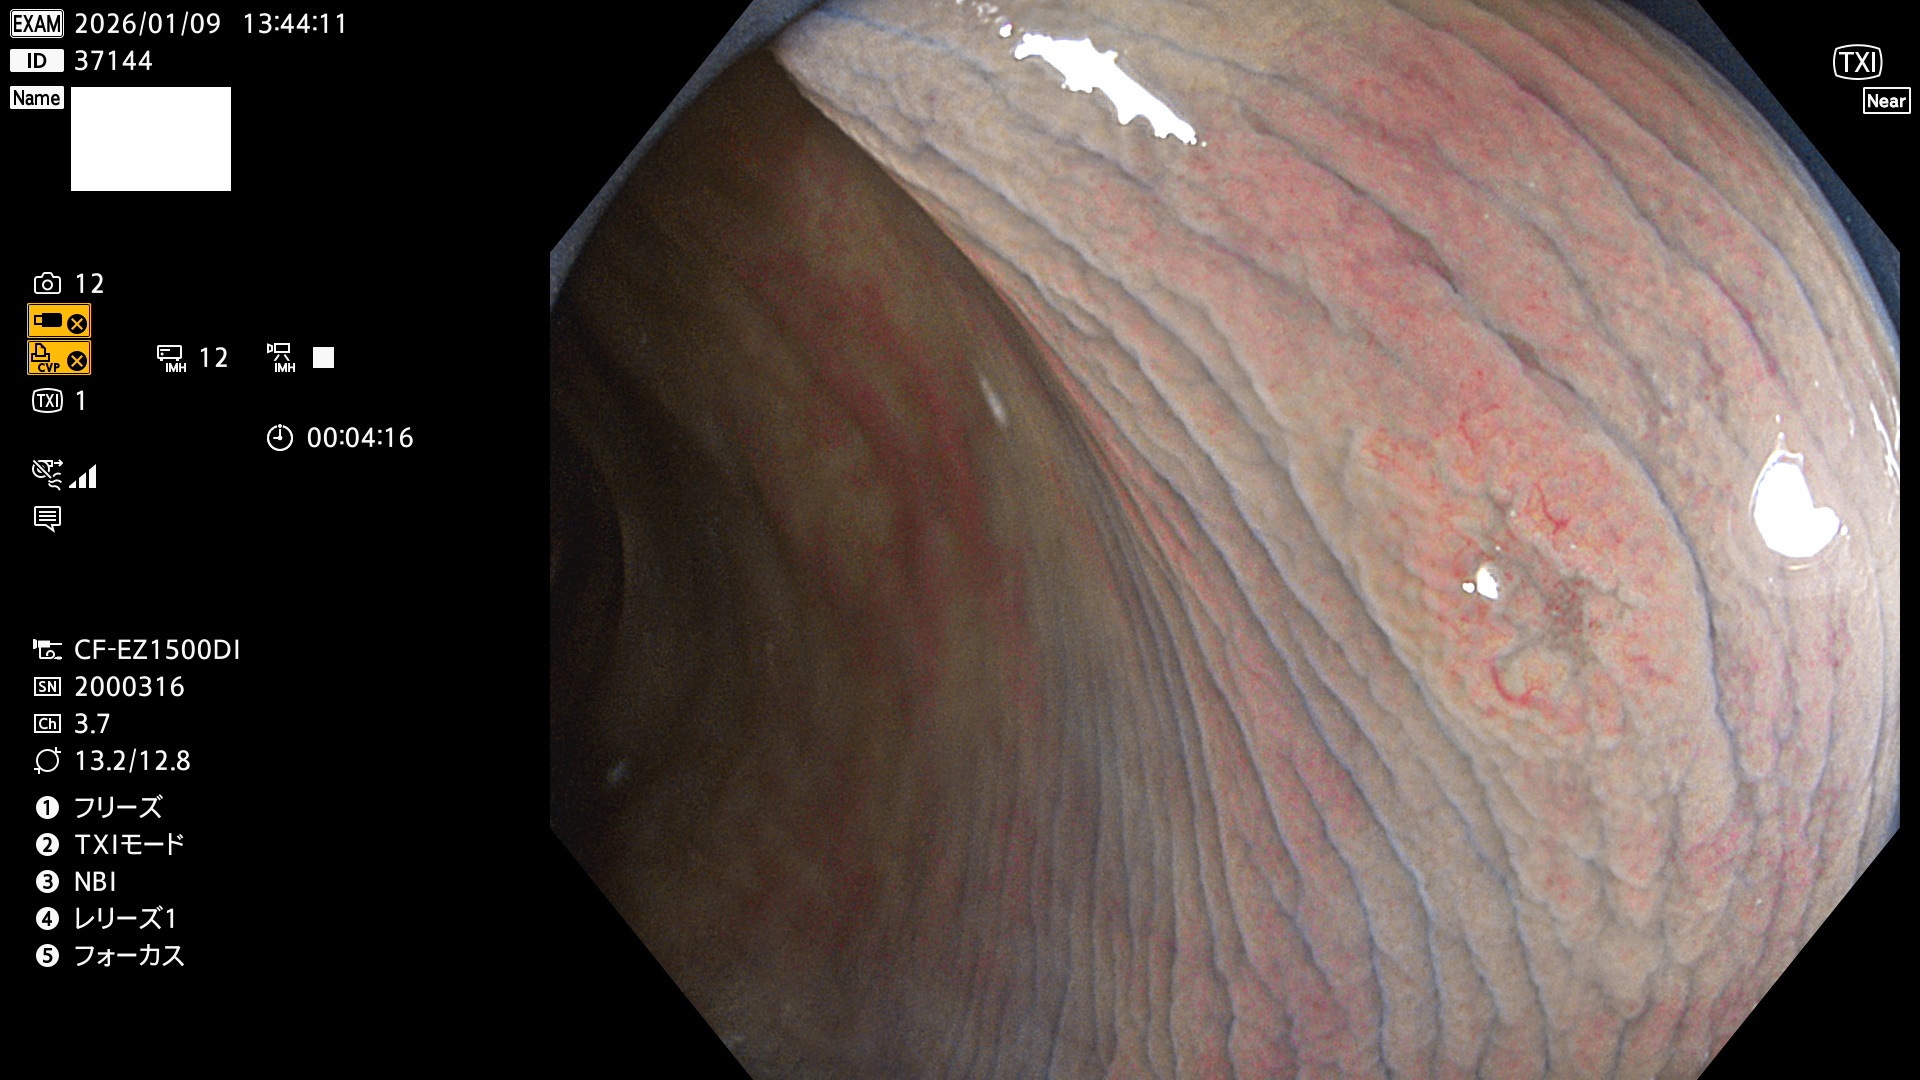

完全に平坦な物をUb、陥凹している物をUcと呼びます。Ubは認識が困難で、Ucはびらん(炎症)と紛らわしいために見落とされやすく、「内視鏡後・大腸癌」の原因になります。

毎週の検査(木・金・土・日)に発見されたUbとUc型・腺腫を、その週の日曜の夜にUPし1週間、提示します。

写真公開の目的は「透明性・信憑性の担保」ですが、公開を希望されない方はメールで御連絡下さい。直ちに削除いたします。

2026年1月8日〜1月11日の4日間(40件)6個 (Uc_ADR=6個/40人=15%)